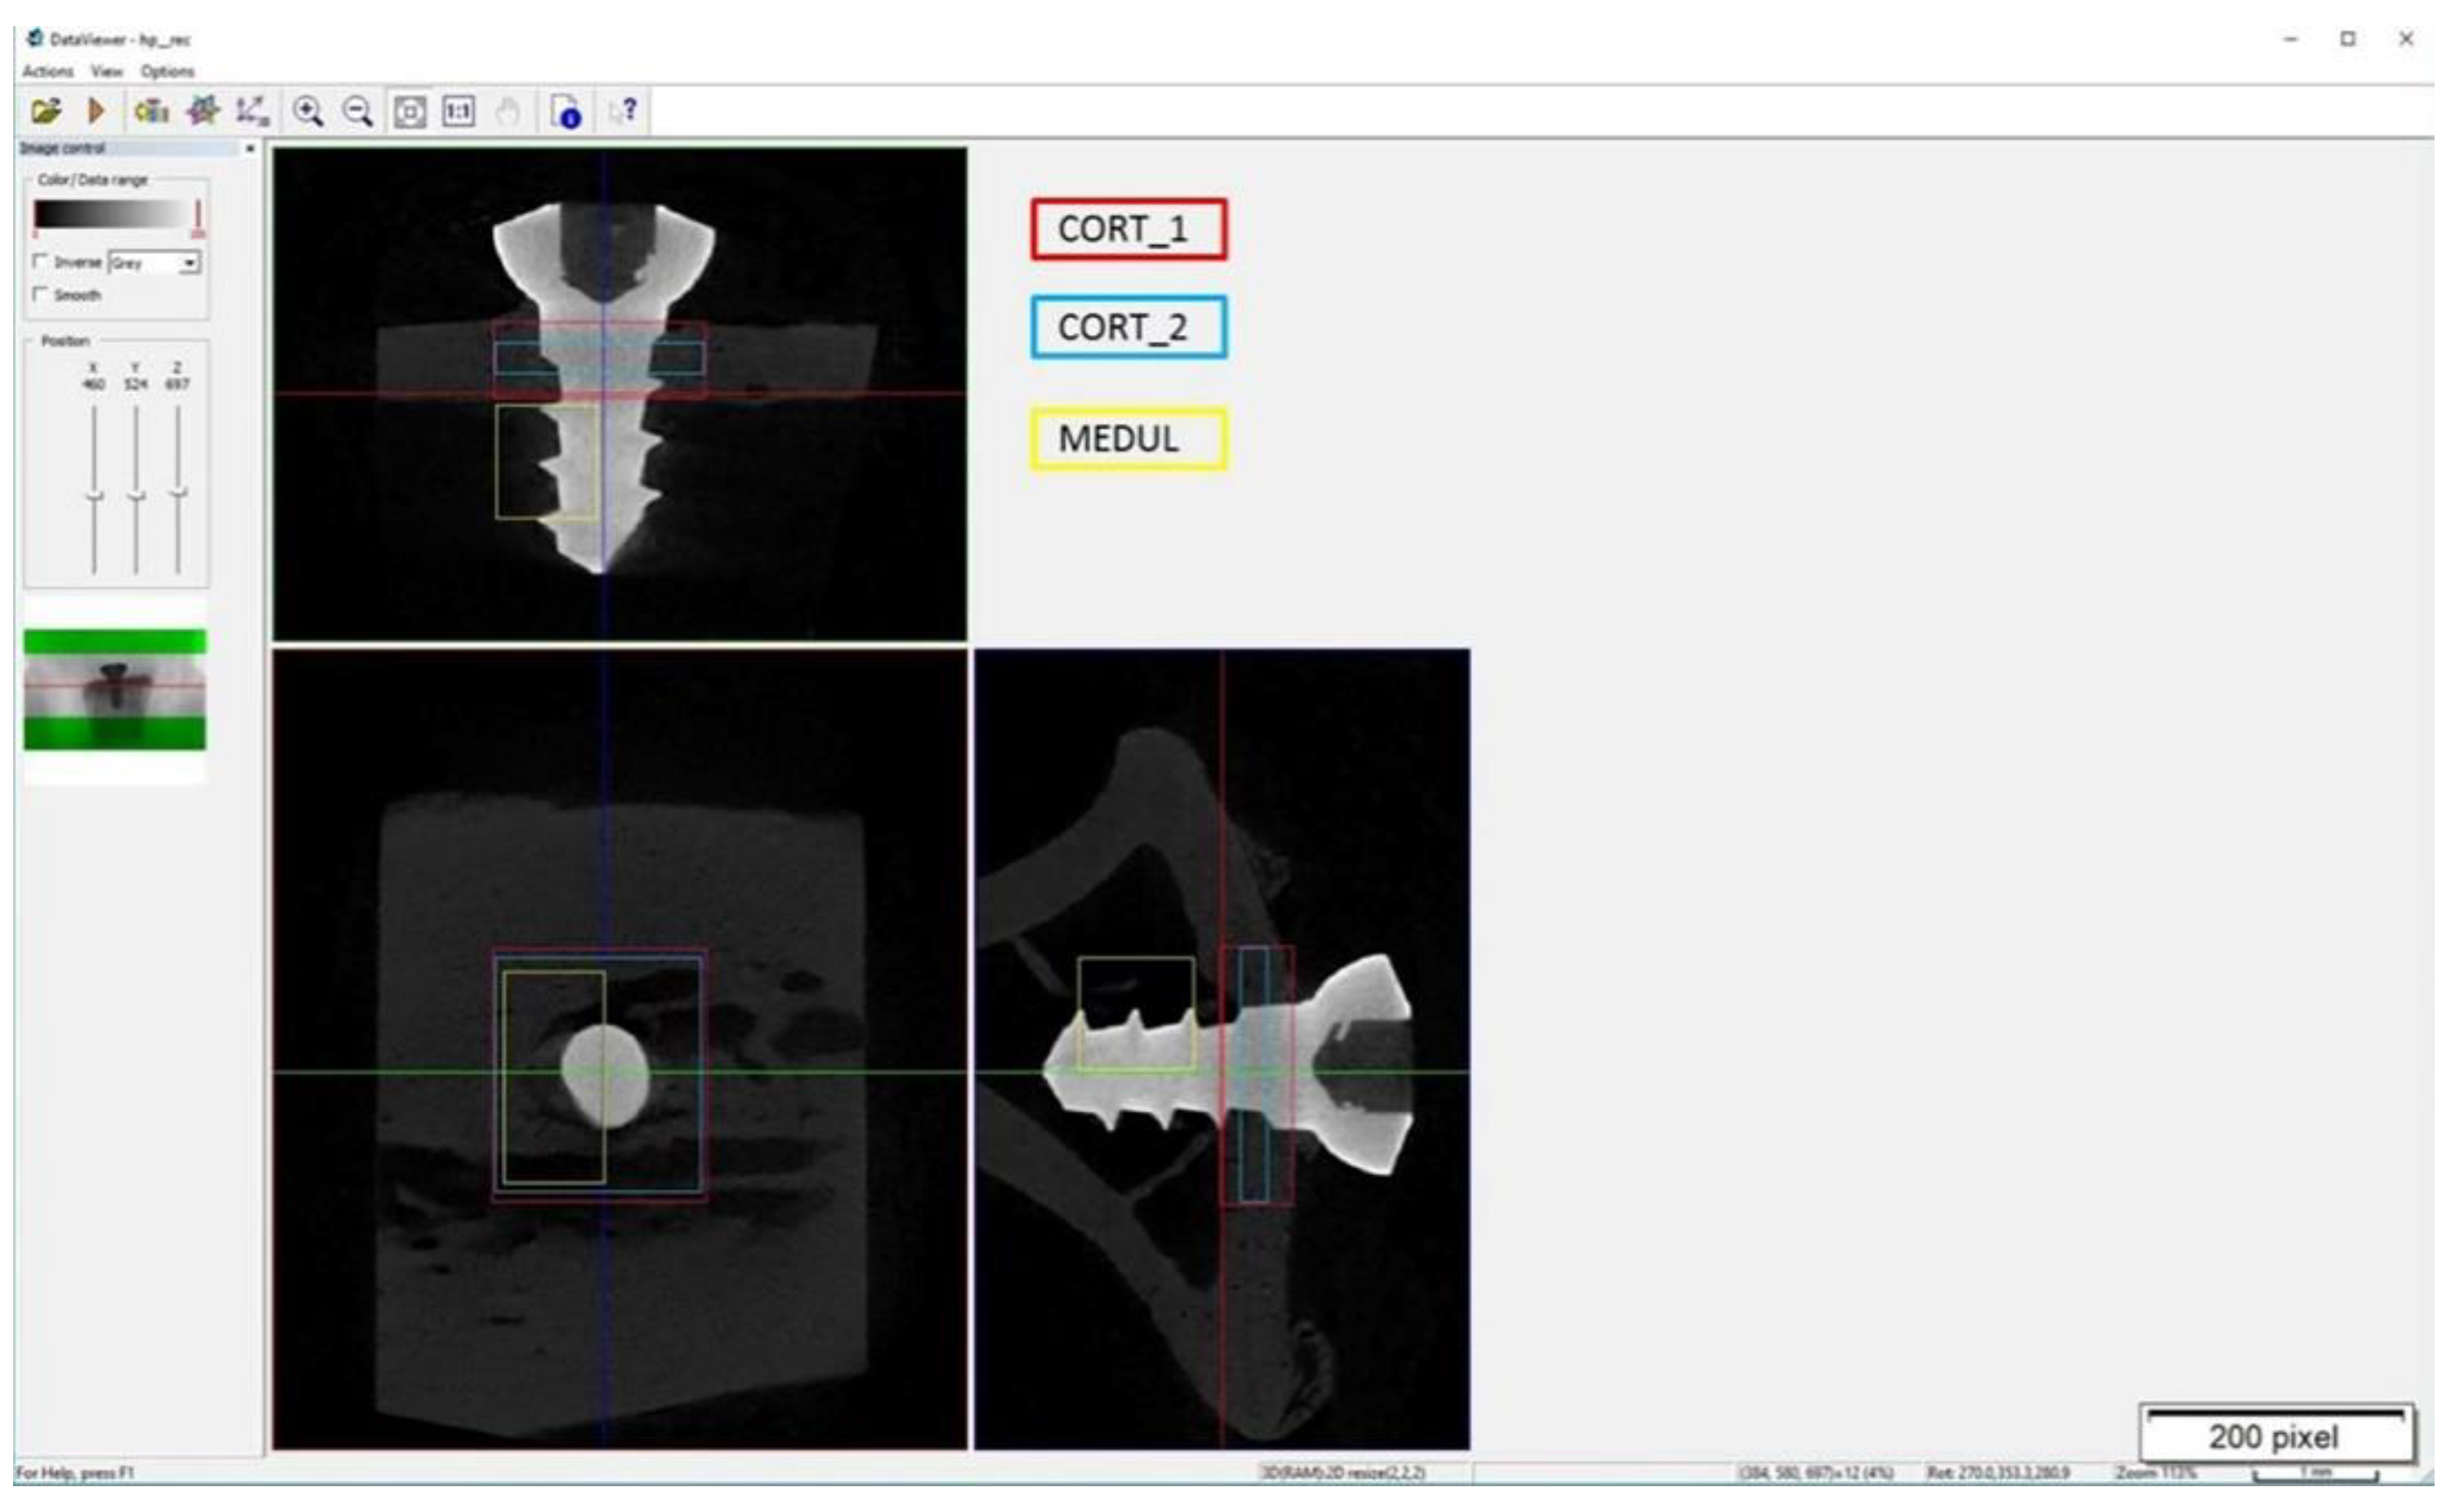

2.7.2. Microtomography